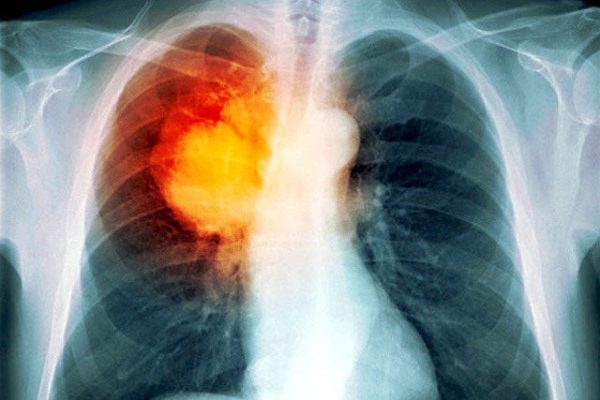

Triệu chứng điển hình của lao phổi đó là ho. Bệnh nhân ho trên ba tuần không phải do viêm phổi, viêm phế quản, giãn phế quản, ung thư phổi mà dùng thuốc kháng sinh không khỏi thì phải nghĩ tới bệnh lao. Đặc biệt, nếu có triệu chứng ho ra máu cần đi kiểm tra ngay để xác định sớm bệnh lý từ đó có phương pháp điều trị phù hợp vì nó có thể là biểu hiện của nhiều loại bệnh như từ các bệnh phổi – phế quản (viêm phổi, viêm phế quản, áp xe phổi, ung thư phổi, phế quản…) đến các bệnh ngoài đường hô hấp như tim mạch (suy tim, tăng huyết áp…), bệnh toàn thân (rối loạn đông máu, chảy máu, thiếu hụt vitamin C…).

Ho ra máu là một dấu hiệu cho thấy vi khuẩn lao đã thâm nhiễm vào trong phổi và bắt đầu phá hủy phổi. Sự phá hủy này diễn ra theo chiều hướng phá tan các cấu trúc và làm thủng mạch máu. Ban đầu có thể chỉ là các mạch máu nhỏ ở phế nang. Sau đó là đến các mạch máu lớn. Điều này khiến máu luôn chảy ra ở trong phổi, tại một số vị trí vi khuẩn lao đã phá hủy. Tại một thời điểm, số lượng máu chảy ra rất nhỏ, nhưng tính trong cả ngày thì lại rất lớn. Người bệnh lao ho ra máu không thể tự cầm và chảy máu diện rộng. Khi vi khuẩn lao phá hủy một mạch máu lớn, lượng máu sẽ chảy ra ồ ạt hoặc khi lượng máu chảy tích tụ quá nhiều lượng máu này sẽ làm bít tắc các đường phế quản trên diện rộng, khiến người bệnh bị tắc thở, suy tuần hoàn và dẫn đến tử vong.